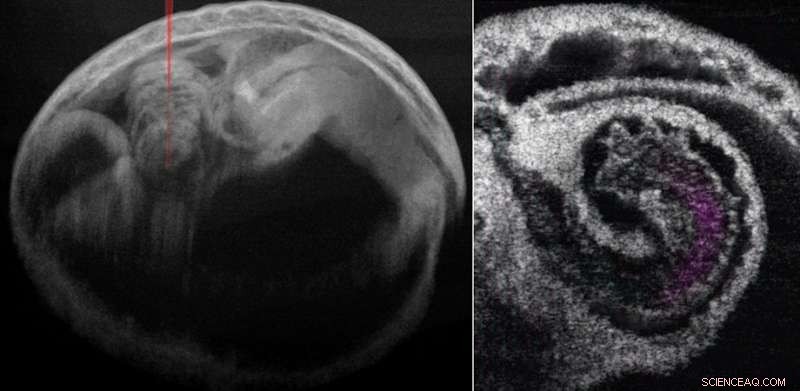

Mouse embryo and heart with blood flow. Credit: Wang and Larina

The unique imaging scales and dynamic contrasts offered by OCT enable millimeter-level imaging depth with a microscale resolution that is ideal for capturing the entire mouse heart at mid-gestation stages. OCT also provides a clear view of fine cardiac structures as well as blood flow. The high imaging speed of OCT together with post-acquisition synchronization allows reconstructing the fast dynamics of the beating heart.